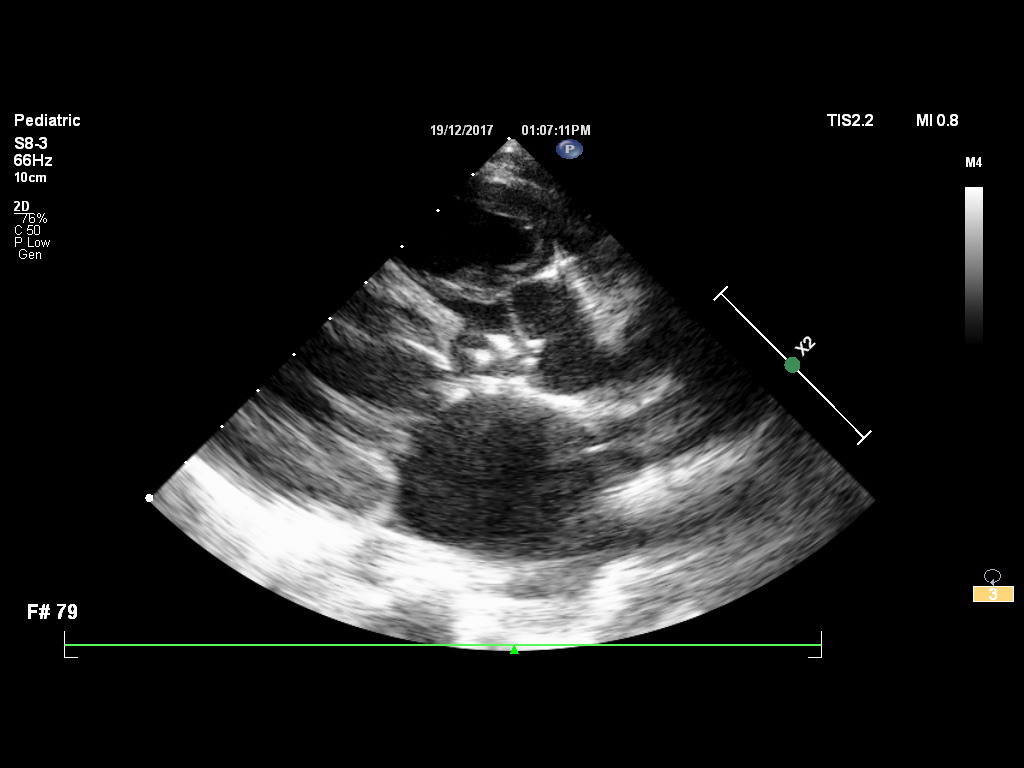

Non-interventional cardiology focuses on diagnosing, monitoring, and managing heart diseases without surgical or catheter-based procedures. It involves the use of non-invasive or minimally invasive techniques such as echocardiography, treadmill stress tests, Holter monitoring, and ambulatory blood pressure monitoring to assess heart function.